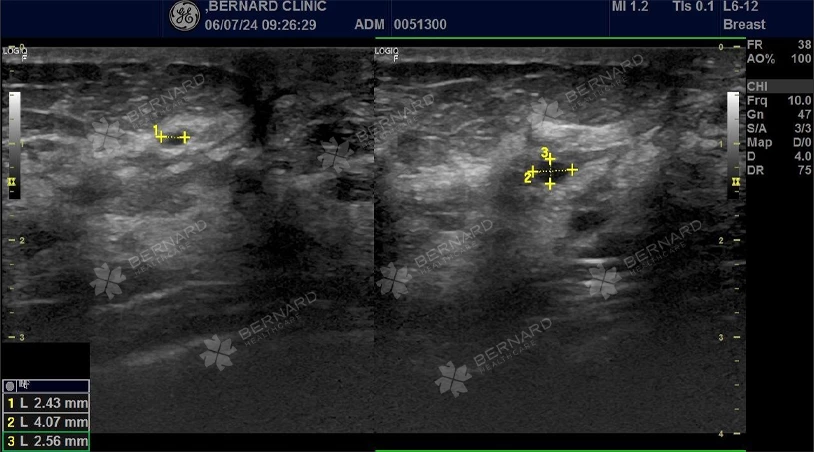

Trong lần thăm khám sức khỏe tổng quát tại Bernard Healthcare cách đây một năm, bà T. được phát hiện có những tổn thương nguy cơ cao ở tuyến vú. Đặc biệt là một sang thương lớn tại vị trí 6 giờ, cách núm vú trái 2cm, bờ không đều, kích thước 12.2 x 9.2mm, được phân loại BIRADS 4.

Trong đợt khám sức khỏe lần này, bệnh nhân được bác sĩ Bernard thuyết phục thực hiện các cận lâm sàng chuyên sâu để đánh giá lại tình trạng bệnh lý. Kết quả siêu âm vú cho thấy, tình trạng bệnh đã trầm trọng hơn năm trước:

- Rải rác tổn thương cũ phân loại BIRADS 2 và BIRADS 3 ở cả 2 vú.

- Kích thước sang thương cũ đã phát triển lớn hơn rất nhiều.

Cụ thể tại vị trí 7h, cách núm vú trái 2cm, cách mặt da d# 8mm, có cấu trúc echo hỗn hợp dạng đặc, kích thước 33x27x32mm, vùng đáy có thoái hóa nang kích thước, 22x12mm, trục ngang, bờ tua gai có vôi hóa đa hình, tăng sinh mạch máu bên trong, phân loại BIRADS 5.